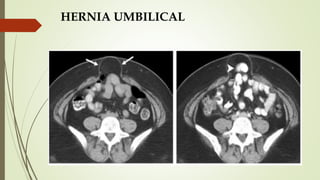

HERNIA UMBILICAL

 Protrusión del contenido abdominal (grasa epiploica ±

intestino) en o a través de la pared abdominal anterior

por el anillo umbilical.

 Congénita/Adquirida.

 Aumento de la presión intraabdominal: obesidad,

gestación múltiple, ascitis.

 DIAGNÓSTICOS DIFERENCIALES:

 Onfalocele: defecto congénito en la pared abdominal a

nivel del ombligo.

 Hernia ventral: epigástricas encima del ombligo,

hipogástricas debajo.

 Hernia de Spiegel: protruye en la línea semilunar y el

borde lateral del músculo recto.